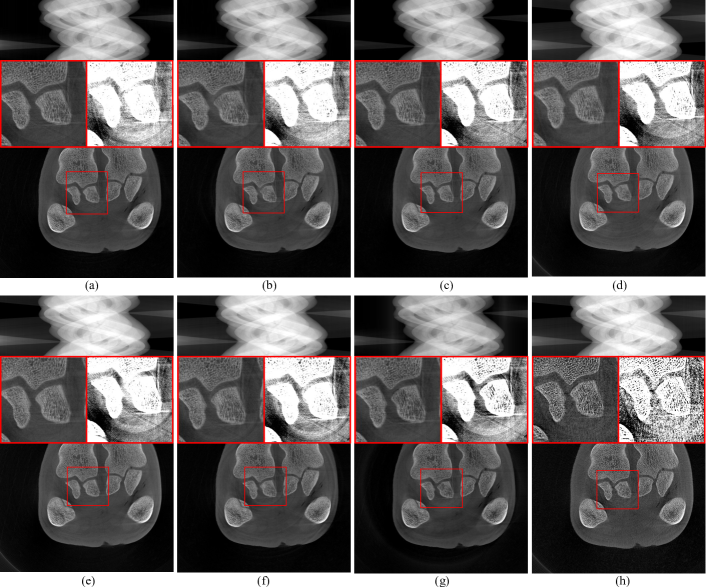

To verify the effectiveness of the two unidirectional gradient constraints and their role in removing ring artifacts from CT images through the sorted sinogram, we used the simulated sinogram shown in Fig. 6 (b). Fig. 11 presents the results obtained by applying different unidirectional gradient constraints to INR, with the number of training iterations fixed at 10,000. The first rows of Fig. 11 show the INR-parameterized IS, respectively, with PSNR and SSIM scores annotated in the figures. The second rows display the profile lines of the 200th row. The green lines represent the reference profile, while the red lines represent the profile lines of the INR-parameterized IS.

Figure 11: Impact of unidirectional gradient constraints on INR-parameterized IS: (a) Angular gradient with L1subscript𝐿1L_{1} constraint applied to SA only; (b) Detector gradient with L2subscript𝐿2L_{2} constraint applied to IS only; (c) Combined angular gradient with L1subscript𝐿1L_{1} constraint on SA and detector gradient with L2subscript𝐿2L_{2} constraint on IS; (d) Combined angular gradient with L1subscript𝐿1L_{1} constraint on SA and weighted detector gradient with L2subscript𝐿2L_{2} constraint on IS; (e) Unsorted IS and SA with combined angular gradient and L1subscript𝐿1L_{1} constraint on SA and detector gradient with L2subscript𝐿2L_{2} constraint on IS. The disparity range is set to [0, 1].

From the observations in Fig. 11 (a) and Fig. 11 (b), it is clear that the IS shown in Fig. 11 (a) exhibits significant stripe artifacts. However, the IS of Fig. 11 (b) shows less prominent stripe artifacts, although the profile plot reveals that the IS profile is overly smooth. This indicates that applying only the angular direction gradient L1subscript𝐿1L_{1} constraint on the SA is insufficient for effectively removing stripe artifacts. Adding a gradient L2subscript𝐿2L_{2} constraint in the detector direction on the IS can somewhat reduce stripe artifacts, but may also lead to overly smooth images. Further observation of Fig. 11 (c) and Fig. 11 (d) shows that all neural network parameterized IS effectively mitigate stripe artifacts. However, the quantitative metrics indicate that the PSNR and SSIM of Fig. 11 (d) are higher than those of Fig. 11 (c), demonstrating the effectiveness of the detector-direction gradient weighting strategy. In contrast, the profile lines of Fig. 11 (e) in columns 200 and 1800 do not effectively match the reference profile. In comparison, the IS profile of Fig. 11 (d) more closely aligns with the reference profile. This suggests that applying a weighted gradient L2subscript𝐿2L_{2} constraint in the detector direction on the sorted IS and an angular gradient L1subscript𝐿1L_{1} constraint on the sorted SA effectively removes stripe artifacts while maintaining image edge sharpness. Comparing Fig. 7 (f) and Fig. 11 (d) reveals that the use of the residual compensation strategy further enhances the PSNR.